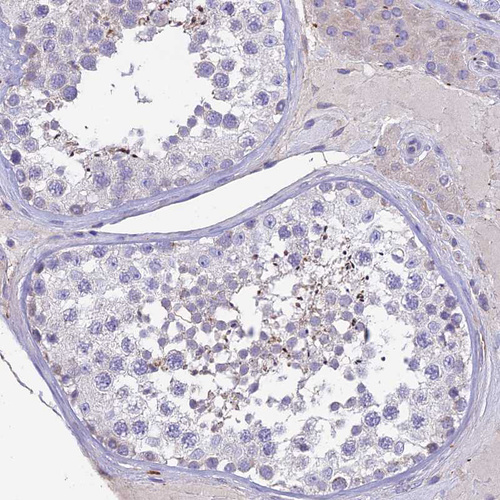

Immunohistochemistry analysis in human duodenum and testis tissues using HPA021826 antibody. Corresponding HSD17B2 RNA-seq data are presented for the same tissues.